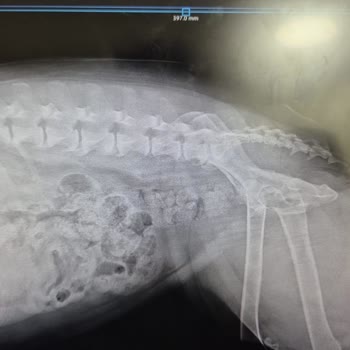

Suna Dumankaya Gebze şubesinde yüz bölgesi lazere gidiyordum. Son gittiğim seansta yanak ve dudak altım yandı. Su kabarcıkları oluştu yüzümde ve şişti ödem yaptı. Ücret iadesinin yapılmasını ve tedavi için ilaç ücretimin karşılanmasını istedim. Cevap dahi verilmedi.

ödem